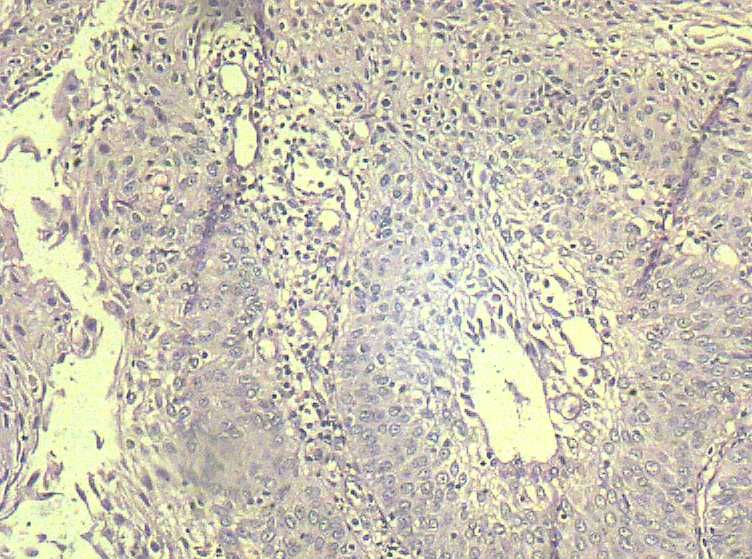

33岁 宫颈刮片看上去很像腺上皮病变,报了AGC 建议活检。 活检取自宫颈,图片如下:请帮忙看下,谢谢!

鳞状上皮增厚,乳头状增生,并见挖空样细胞。提示HPV感染。

有不典型增生, 不知道大家有没有看到。  如果有不典型和上面的图像可或直接报 :尖锐湿疣伴不典型增生。